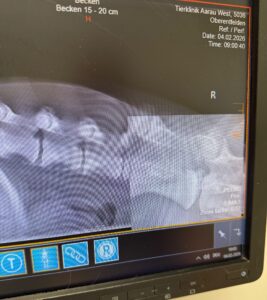

Tierklinik – die Erste

Heute Morgen war Mia in der Tierklink Aarau-West für weitere Untersuchungen und Röntgenaufnahmen. Ohne Frühstück ist alles doof, aber Mia hat ganz brav mitgemacht. Nüchtern